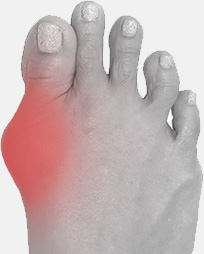

С целью устранения Hallus valgus (бурсита) и негативных симптомов, сопровождающих деформацию ступней, успешно применяется магнитотерапия. Магнитотерапия – уникальный метод физиотерапевтического лечения с помощью воздействия на организм постоянным, переменным или бегущим магнитным полем. Процедура является безопасной и не вызывает болезненных ощущений.

Чтобы купировать воспалительный процесс, достаточно использовать магнитную шину MAGNETFIX ежедневно в течение 3-5 часов. Это способствует не только выравниванию фаланг пальцев и уменьшению деформации, но также благодаря воздействию магнитов происходит стимуляция нервных окончаний, повышается тонус тканей, улучшается кровообращение. MAGNETFIX фиксирует большой палец в нужном положении, снижает нагрузку на ступни, купирует боль, облегчает ходьбу и возвращает здоровья ступням.